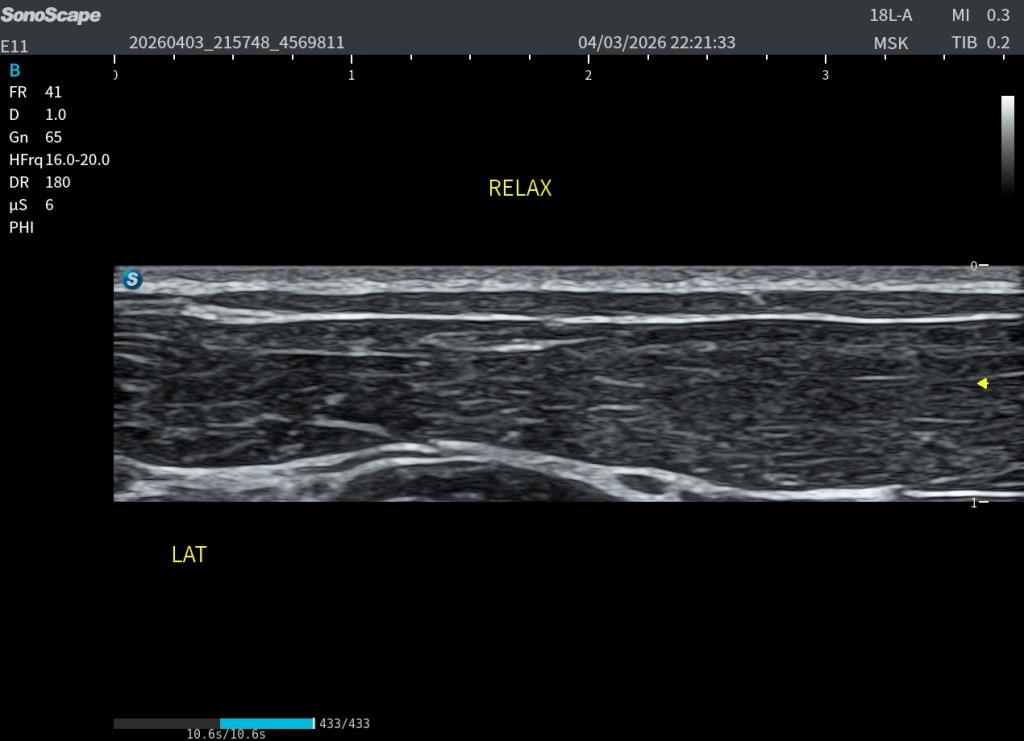

El Platisma se presta especialmente bien a la evaluación mediante técnicas de campo extendido. Utilizando el modo panoramic view, es posible realizar un recorrido continuo del músculo y obtener una visión global de su extensión, algo muy útil dada su morfología plana y superficial.

La exploración puede realizarse en eje axial (corte corto respecto al cuello), desplazando la sonda de forma progresiva a lo largo del trayecto del músculo. Esto permite visualizar su continuidad lateral y entender mejor su disposición en el plano subcutáneo. También puede intentarse un estudio bilateral, tratando de integrar ambos lados en una única imagen panorámica.

Sin embargo, esta técnica presenta cierta dificultad al atravesar la región central del cuello, especialmente sobre la tráquea, donde la superficie es más irregular y la transmisión del movimiento de la sonda es menos homogénea. Esto puede generar artefactos o discontinuidades en la reconstrucción de la imagen.

A pesar de estas limitaciones, el platisma, por ser un músculo muy extenso, plano y superficial, se adapta bien a este tipo de exploración, y la panoramic view se convierte en una herramienta especialmente útil para comprender su anatomía global y su continuidad. Podemos medirlo tambien.